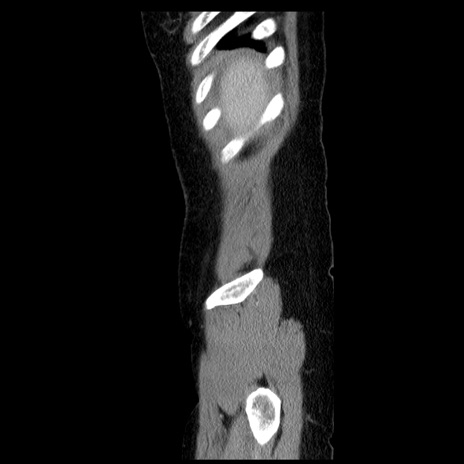

症例6(矢状断像)

【症例】50歳代女性

【主訴】下腹部痛

【現病歴】本日朝より下痢2回あり。 昼食を食べた後、嘔吐3回、下腹部痛認め、症状軽快せず、当院救急搬送。

最終食事:本日昼(生ものなし)。 昨日の夜、刺身を食ぺたとのこと。周囲に同様の症状の者なし。普段、排便は毎日あるとのこと。

【既往歴】卵巣癌術後(8年前に当院で卵巣摘出)

【身体所見】 意識清明、腹部:平坦、腸蠕動音→、やや硬、下腹部自発痛・圧痛あり、反跳痛あり、筋性防御なし。

【データ】WBC 16000、CRP 0.01